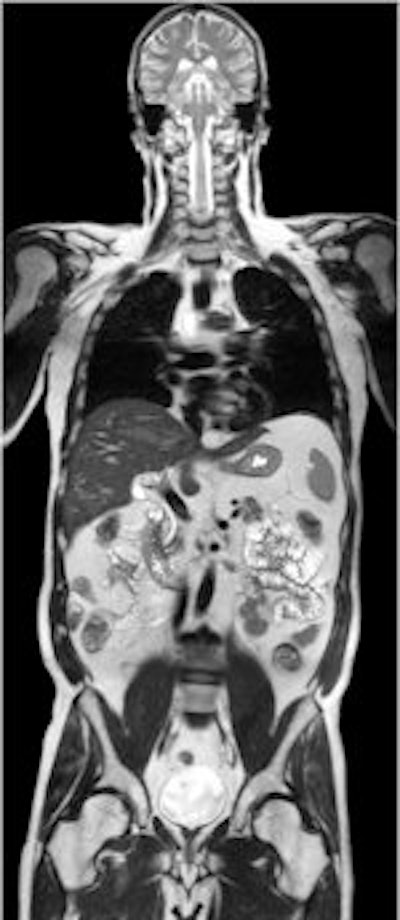

MR investigations of the spine and brain tend to be common sources of errors. Image courtesy of Philips Healthcare.